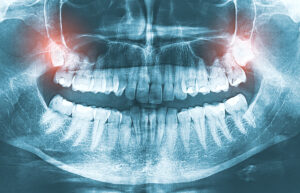

気になる方は、歯科医院でレントゲン撮影を行い、自分の親知らずの位置や向きを確認してみましょう。